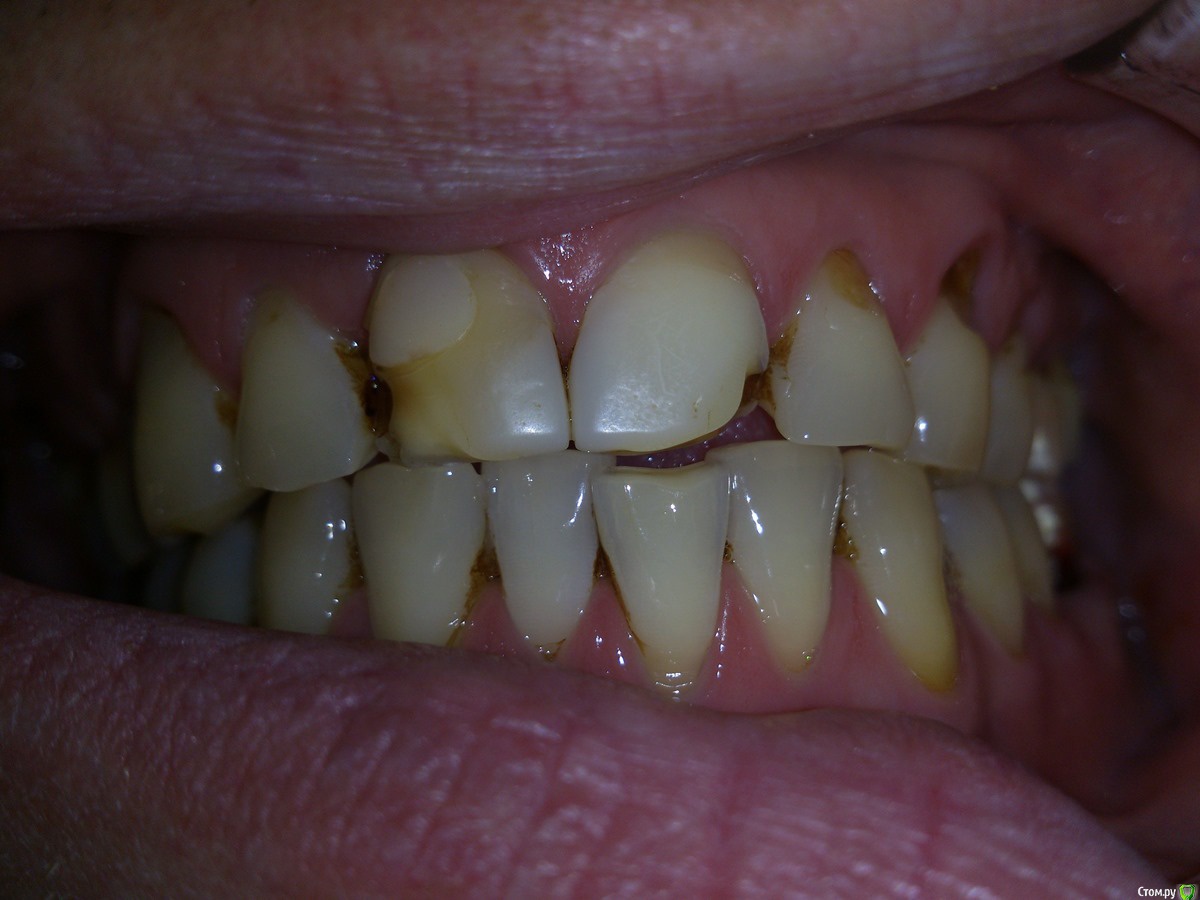

SanderS Опубликовано 6 февраля, 2016 Поделиться Опубликовано 6 февраля, 2016 Пациенту не нравится фронт и пришеечные дефекты, перелечены несколько зубов. Из анамнеза - привычка "стискивать зубы", или как говорит - "попадаю на какой то зуб и начинаю двигать челюсть влево вправо не задумываясь", появилось лет 10 назад, сейчас 35.Возможно обойтись без тотала с каппой, или не браться вообще? Ссылка на комментарий

SanderS Опубликовано 8 февраля, 2016 Автор Поделиться Опубликовано 8 февраля, 2016 те что после перелечивания естественно будут покрываться коронками, нижний моляр имплантат, если пришеечные дефекты реставрировать композитом при условии восстановления клыковой направляющей + каппа, не повыпадают ли они? Высота у него вроде не снижена, за счет компенсации. Ссылка на комментарий

Ronin Опубликовано 8 февраля, 2016 Поделиться Опубликовано 8 февраля, 2016 те что после перелечивания естественно будут покрываться коронками, нижний моляр имплантат, если пришеечные дефекты реставрировать композитом при условии восстановления клыковой направляющей + каппа, не повыпадают ли они? Высота у него вроде не снижена, за счет компенсации.Пломбы не простоят долго, здесь даже подсказка, что клиновидные дефекты, повсеместно, что перегрузка, упругие деформации в действии имеют место быть. Как временное мероприятие, если средств нет пока заниматься, но лучше уточнить высоту и оставить все на временных до возможности финансово заняться, или билдап сделать на боковых из композита самостоятельно или по вакс-апу, лучше второе. Ссылка на комментарий